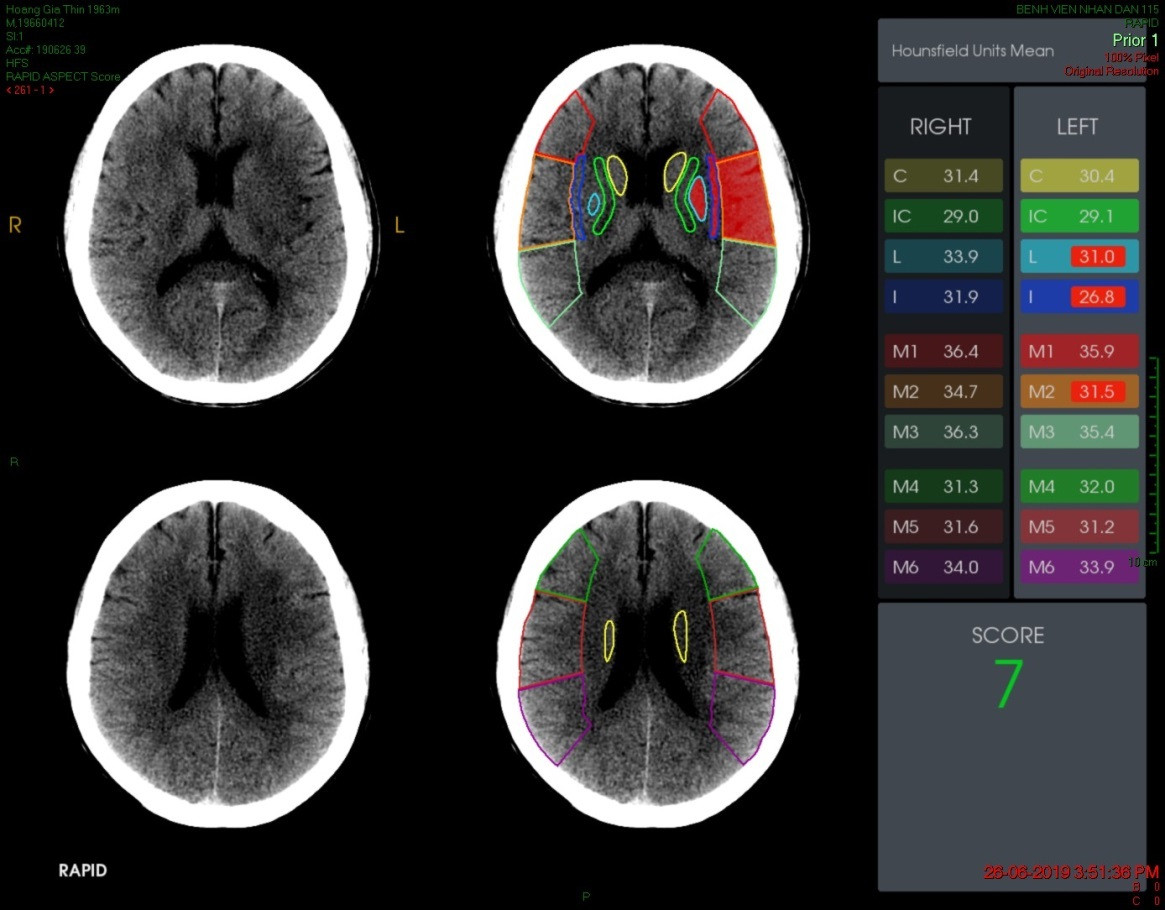

| Phần mềm RAPID giúp mở rộng cửa sổ trong điều trị đột quỵ cho người bệnh |

Bên cạnh đó, bệnh viện còn triển khai phần mềm trí tuệ nhân tạo RAPID trong chẩn đoán và điều trị đột quỵ. Công nghệ này hỗ trợ đưa ra quyết định điều trị đột quỵ và cho phép mở rộng cửa sổ điều trị lên đến 24 giờ. Có thể hiểu đơn giản, bệnh nhân đột quỵ đến bệnh viện sau giờ vàng (từ 6 - 24 giờ), phần mềm RAPID có thể giúp chọn 56% bệnh nhân được can thiệp nội mạch. Kết quả, có 51,2% người bệnh quay trở lại cuộc sống bình thường. Đến nay, kỹ thuật can thiệp lấy huyết khối nhờ phần mềm trí tuệ nhân tạo RAPID đã chữa trị thành công cho 792 bệnh nhân.